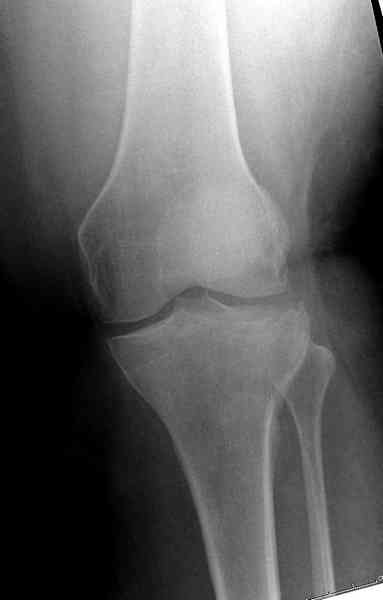

[Ortho] Остеосинтез при импрессионном переломе заднего отдела наружного мыщелка tibia?

Из медиального окна можно приподнять латеральную

импрессию. Фиксация тремя параллельными шурупами в

эпифизарной части над импрессией. Создается крыша,

которая предупредит коллапс. На образовавшуюся полость - костная

пластика из аутокости или синтетический заменитель. Мы применяем

Osteoset в 4-5 мм диаметре таблеточки или иньекционную форму Prodens.